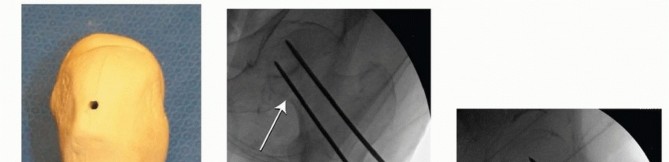

Closed Reduction and Percutaneous Fixation The patient is positioned on the fracture table and reduction is obtained as noted earlier, C-arm visualization is verified, and the leg and hip is prepared and draped in a sterile fashion. Preoperative antibiotics are given. ### Guidewire and Screw Placement Guidewires for cannulated screws are placed in line with the femoral neck axis through poke holes. The wires are placed parallel using a parallel drill guide. The standard screw arrangement is an inverted triangle of three screws. They should be positioned peripherally in the femoral neck with good cortical buttress, particularly against the inferior and posterior neck. Starting points below the lesser trochanter should be avoided owing to risk of subtrochanteric fracture postoperatively ( TECH FIG 1A-C).

TECH FIG 1 • A. Sawbones lateral view of the proximal femur showing configuration for three parallel guidewires before placement of cannulated screws. The wire starting points form an inverted triangle. B. Intraoperative AP fluoroscopic view showing position and depth of the guidewires. The inferior wire runs right along the inferior cortex of the femoral neck—the “calcar” (

arrow

). C. Intraoperative lateral fluoroscopic view showing guidewire position. The posterior wire is directly adjacent to and supported by the posterior cortex of the neck. Care is necessary to ensure that the guidewire does not go outside of the neck and then reenter the femoral head.